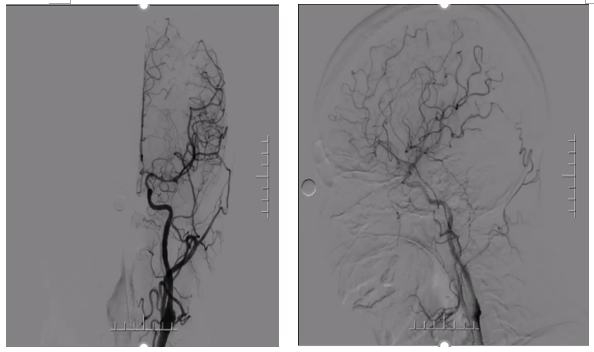

手术方案

病历夹什么径技·第151期|串联营病历夹:京广连营_https://www.jmylbn.com_新闻资讯_第75张

病历夹什么径技·第151期|串联营病历夹:京广连营_https://www.jmylbn.com_新闻资讯_第76张

病历夹什么径技·第151期|串联营病历夹:京广连营_https://www.jmylbn.com_新闻资讯_第77张

<<滑动查看下一张图片>>

• 左侧椎动脉造影见基底动脉起始处闭塞。

• 微导管造影,见基底动脉尖及左侧大脑后动脉显影不良,考虑栓塞。

• 基底动脉近端打开支架,支架形态尚可,局部发白,左侧大脑前动脉P1段栓塞。

• 支架取栓取出一小块栓子,造影见基底动脉起始处重度狭窄。

• 狭窄处予球囊扩张成形,球扩后造影见基底动脉狭窄有所改善。

• 微导管送至左侧大脑后动脉P2段,造影确认真腔后,释放支架,并支架取栓1次。

• 血栓成功取出,基底动脉侧位造影,左侧大脑后动脉再通。

• 正位造影,左侧大脑后动脉再通,无血栓逃逸,基底动脉狭窄改善,未回缩,前向血流正常,观察后结束手术。

手术评估

病历夹什么径技·第151期|串联营病历夹:京广连营_https://www.jmylbn.com_新闻资讯_第78张

病历夹什么径技·第151期|串联营病历夹:京广连营_https://www.jmylbn.com_新闻资讯_第79张

病历夹什么径技·第151期|串联营病历夹:京广连营_https://www.jmylbn.com_新闻资讯_第80张

• 患者术后转入重症医学科,症状一直未有改善,昏迷状,术后第5天家属放弃治疗自动出院。